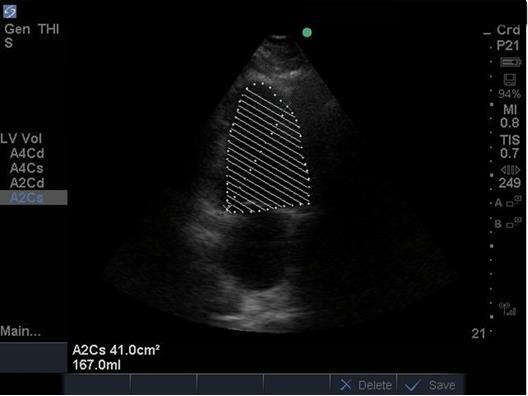

Heart Ejection Fraction (EF) 3 Image